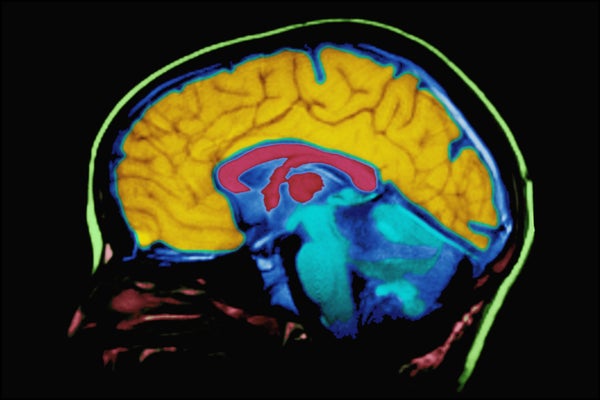

She had come down with encephalitis about six or seven years before, and it had destroyed her hippocampus and surrounding tissues in the center of her brain. And being a science journalist who's written about memory, I already knew what that meant, because there was a famous case in the 1950s of a guy named – he was only known by his initials, H. M., who had the same thing happen to him as a result of surgery. And as a result, he could no longer remember much of his past. He had amnesia, but he also had – he was not able to form new memories going into the future. So he was trapped in this sort of slice of time, and I'd always thought about what a weird state that would be, to be in.

Lemonick: They were trying to cure epilepsy with H. M. They thought that the seizures that he was having, these terrible seizures, were originating in the hippocampus. And it was an experimental surgery to pull out the hippocampus, destroy it and cure the seizures, which it did. Unfortunately, nobody knew that this was the seat of memory.

Lemonick: That happened in the 1950s, and as soon as people realized what had happened to him, he became an object of serious neuroscientific investigation, because nobody knew at that time where memory was located in the brain. Or, how it worked. And suddenly they had a way to get at this problem.

Lemonick: It's ongoing, oh yeah, they've barely scratched the surface, 'cause she poses so many interesting questions that they don't even know what they all are yet. The scientists are still figuring out questions to ask of her, but what we learn from H. M. is that memory is very tied up in this organ within the brain called the hippocampus. It's crucial to forming and retrieving memories, most memories. That we didn't know. We learned from him that procedural memory is located somewhere else, and that was mostly it. With some of these other patients, but especially with Lonny Sue, we're not learning that those simple divisions of memory that I talked about earlier, are actually – they're much more subtle.